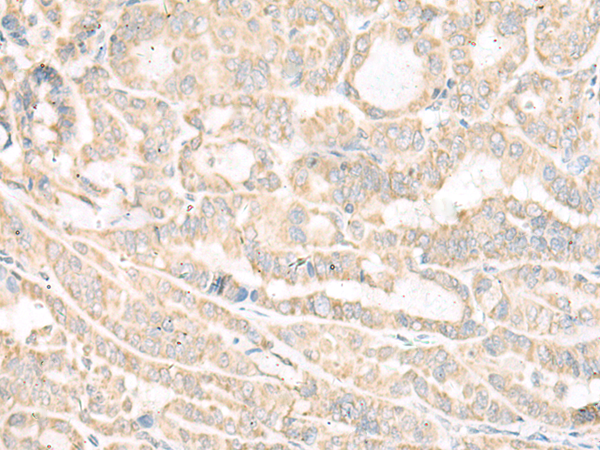

IHC positive control:

Human thyroid cancer and Human cervical cancer

IHC Recommend dilution:

30-150